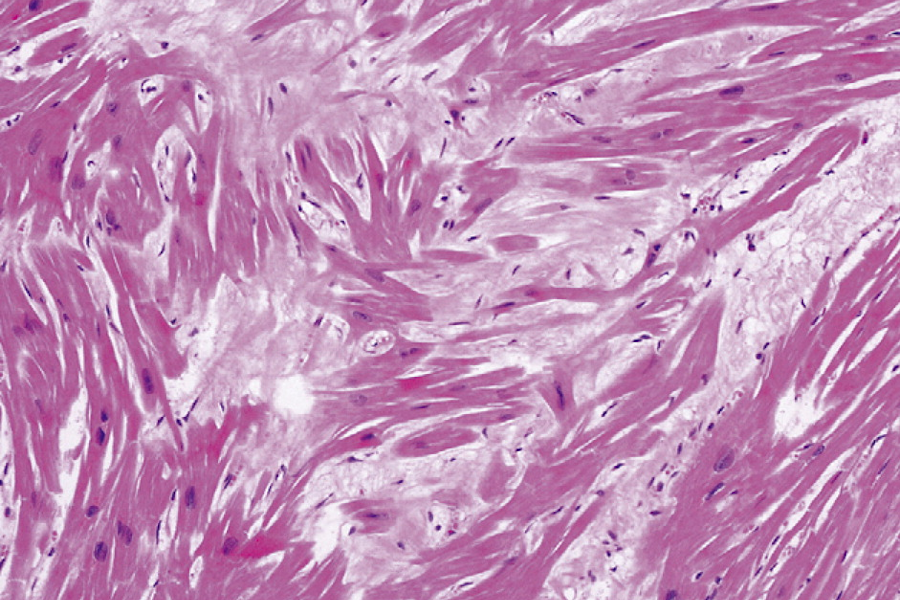

histologische Bilder

adultes Myokard adultes Myokard

hypertensive Herzkrankheit hypertensive Herzkrankheit

hypertrophe Kardiomyopathie hypertrophe Kardiomyopathie

kardiale Amyloidose kardiale Amyloidose

kardiale Hämochromatose kardiale Hämochromatose

Glykogen-Speicherkrankheit Glykogen-Speicherkrankheit

Pathology Residency and Fellowship Program, Brown University, Access 23. October 2022

Elliott P, McKenna WJ (2004) Lancet 363:1881-1891

Internet Pathology Laboratory , University of Utah, Access 23. October 2022

Thoracic Pathology, Cardiac Hemochromatosis, Access 23.October 2022